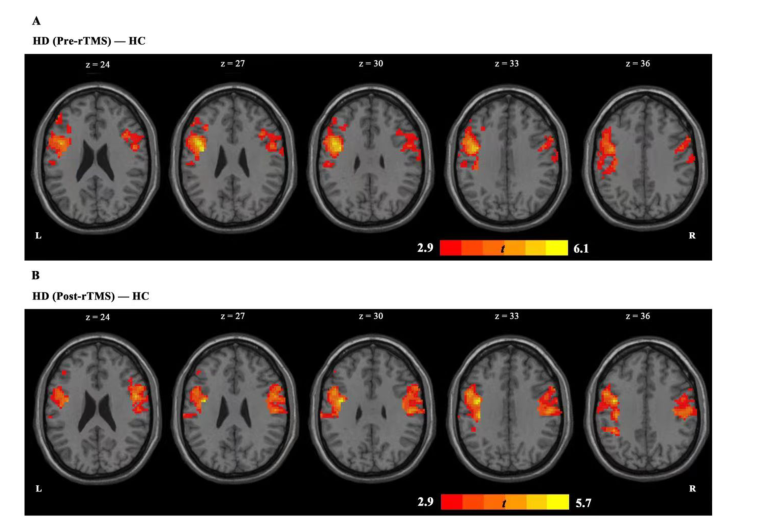

上圖顯示,在基于 PCC 的分析中,我們發現 HD 組與 HC 組相比表現出 PCC-左額下回,PCC-右側中央前回耦聯增加。

在完成 7 個療程的 rTMS 療程后,HD 組的 PCC-左額下回耦合異常增加后出現了減少,并在HC組表現出類似的趨勢。但在治療后,(HDvsHC)pcc-右中央前回耦聯持續存在。